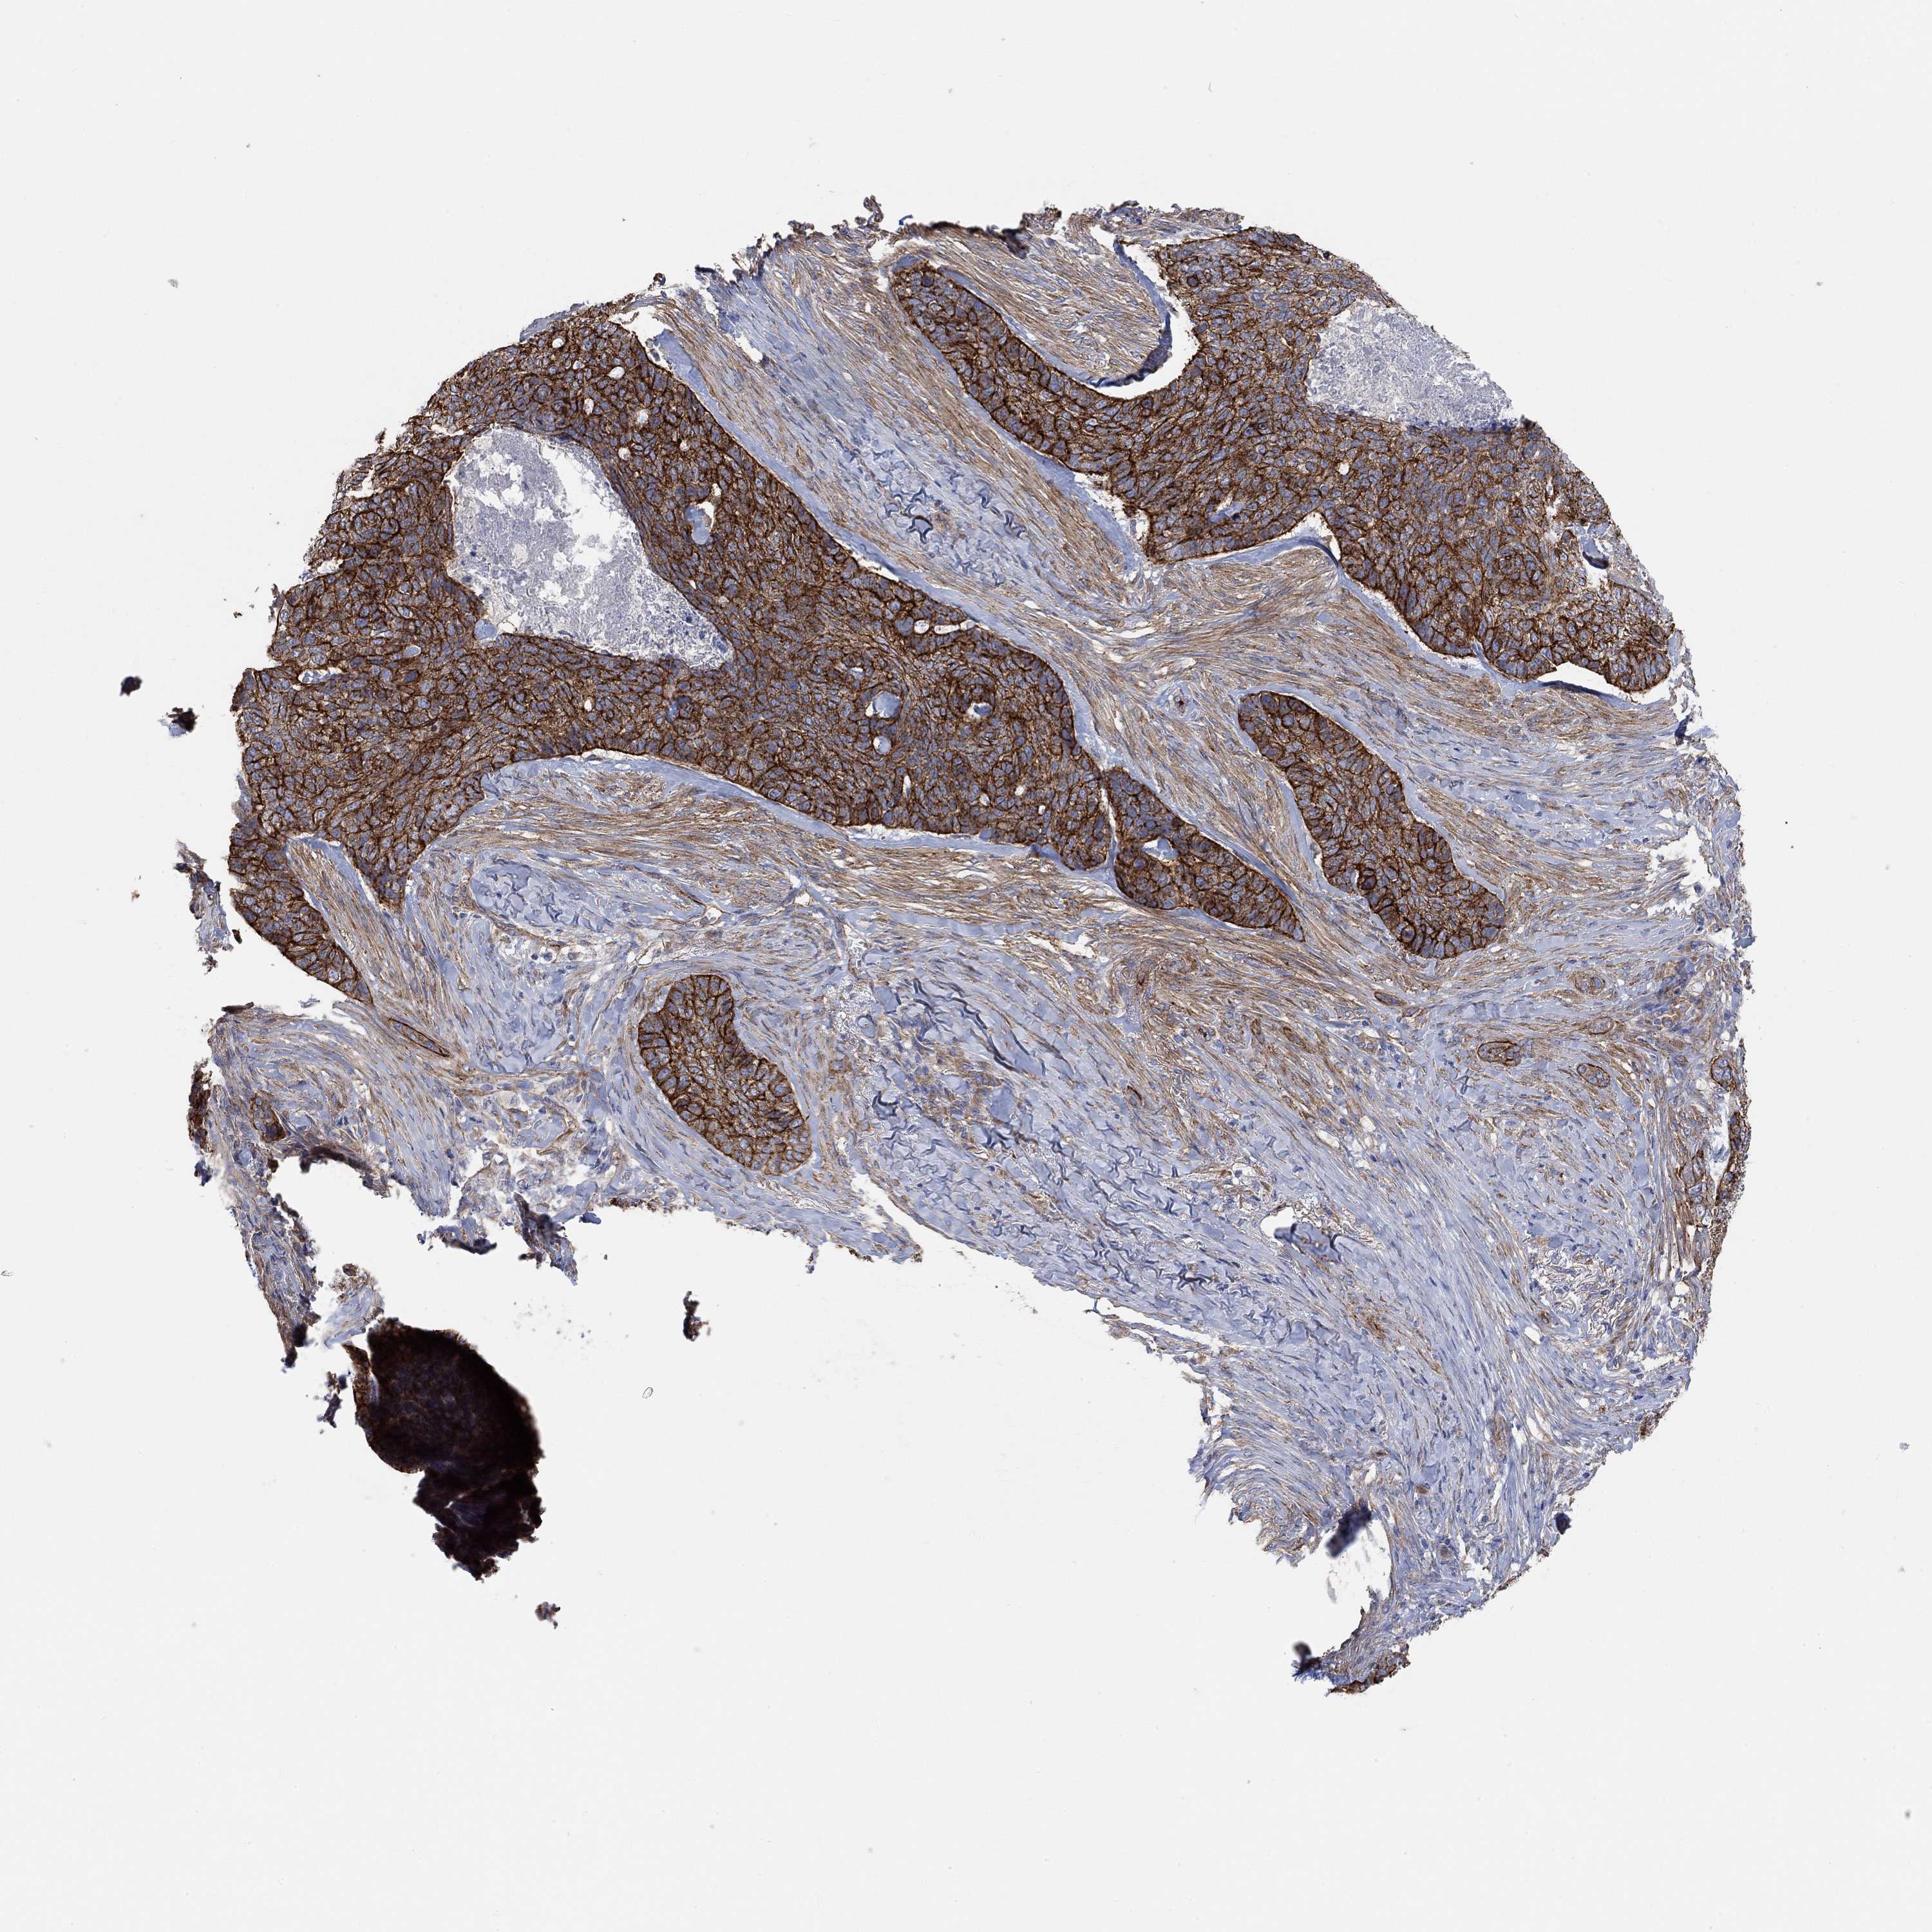

Basal cell and squamous cell cancer

SKIN CANCER - Protein expressioni

A mouse-over function shows sample information and annotation data. Click on an image to view it in a full screen mode. Samples can be filtered based on level of antibody staining by selecting one or several of the following categories: high, medium, low and not detected. The assay and annotation is described here.

Antibody stainingi

Antibody staining in the annotated cell types in the current human tissue is reported as not detected, low, medium, or high, based on conventional immunohistochemistry profiling in selected tissues. This score is based on the combination of the staining intensity and fraction of stained cells.

Each image is clickable and will lead to virtual microscopy that enables deeper exploration of all samples and also displays staining intensity scores, fraction scores and subcellular localization as well as patient and tissue information for each sample.

Antibody HPA004199

Antibody HPA076871

Squamous cell carcinoma, NOS

Basal cell carcinoma